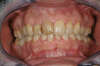

11. RÉALISATION DE 8 FACETTES CÉRAMIQUES SUR LES DENTS DU HAUT - DENTISTE 92400

AVANT